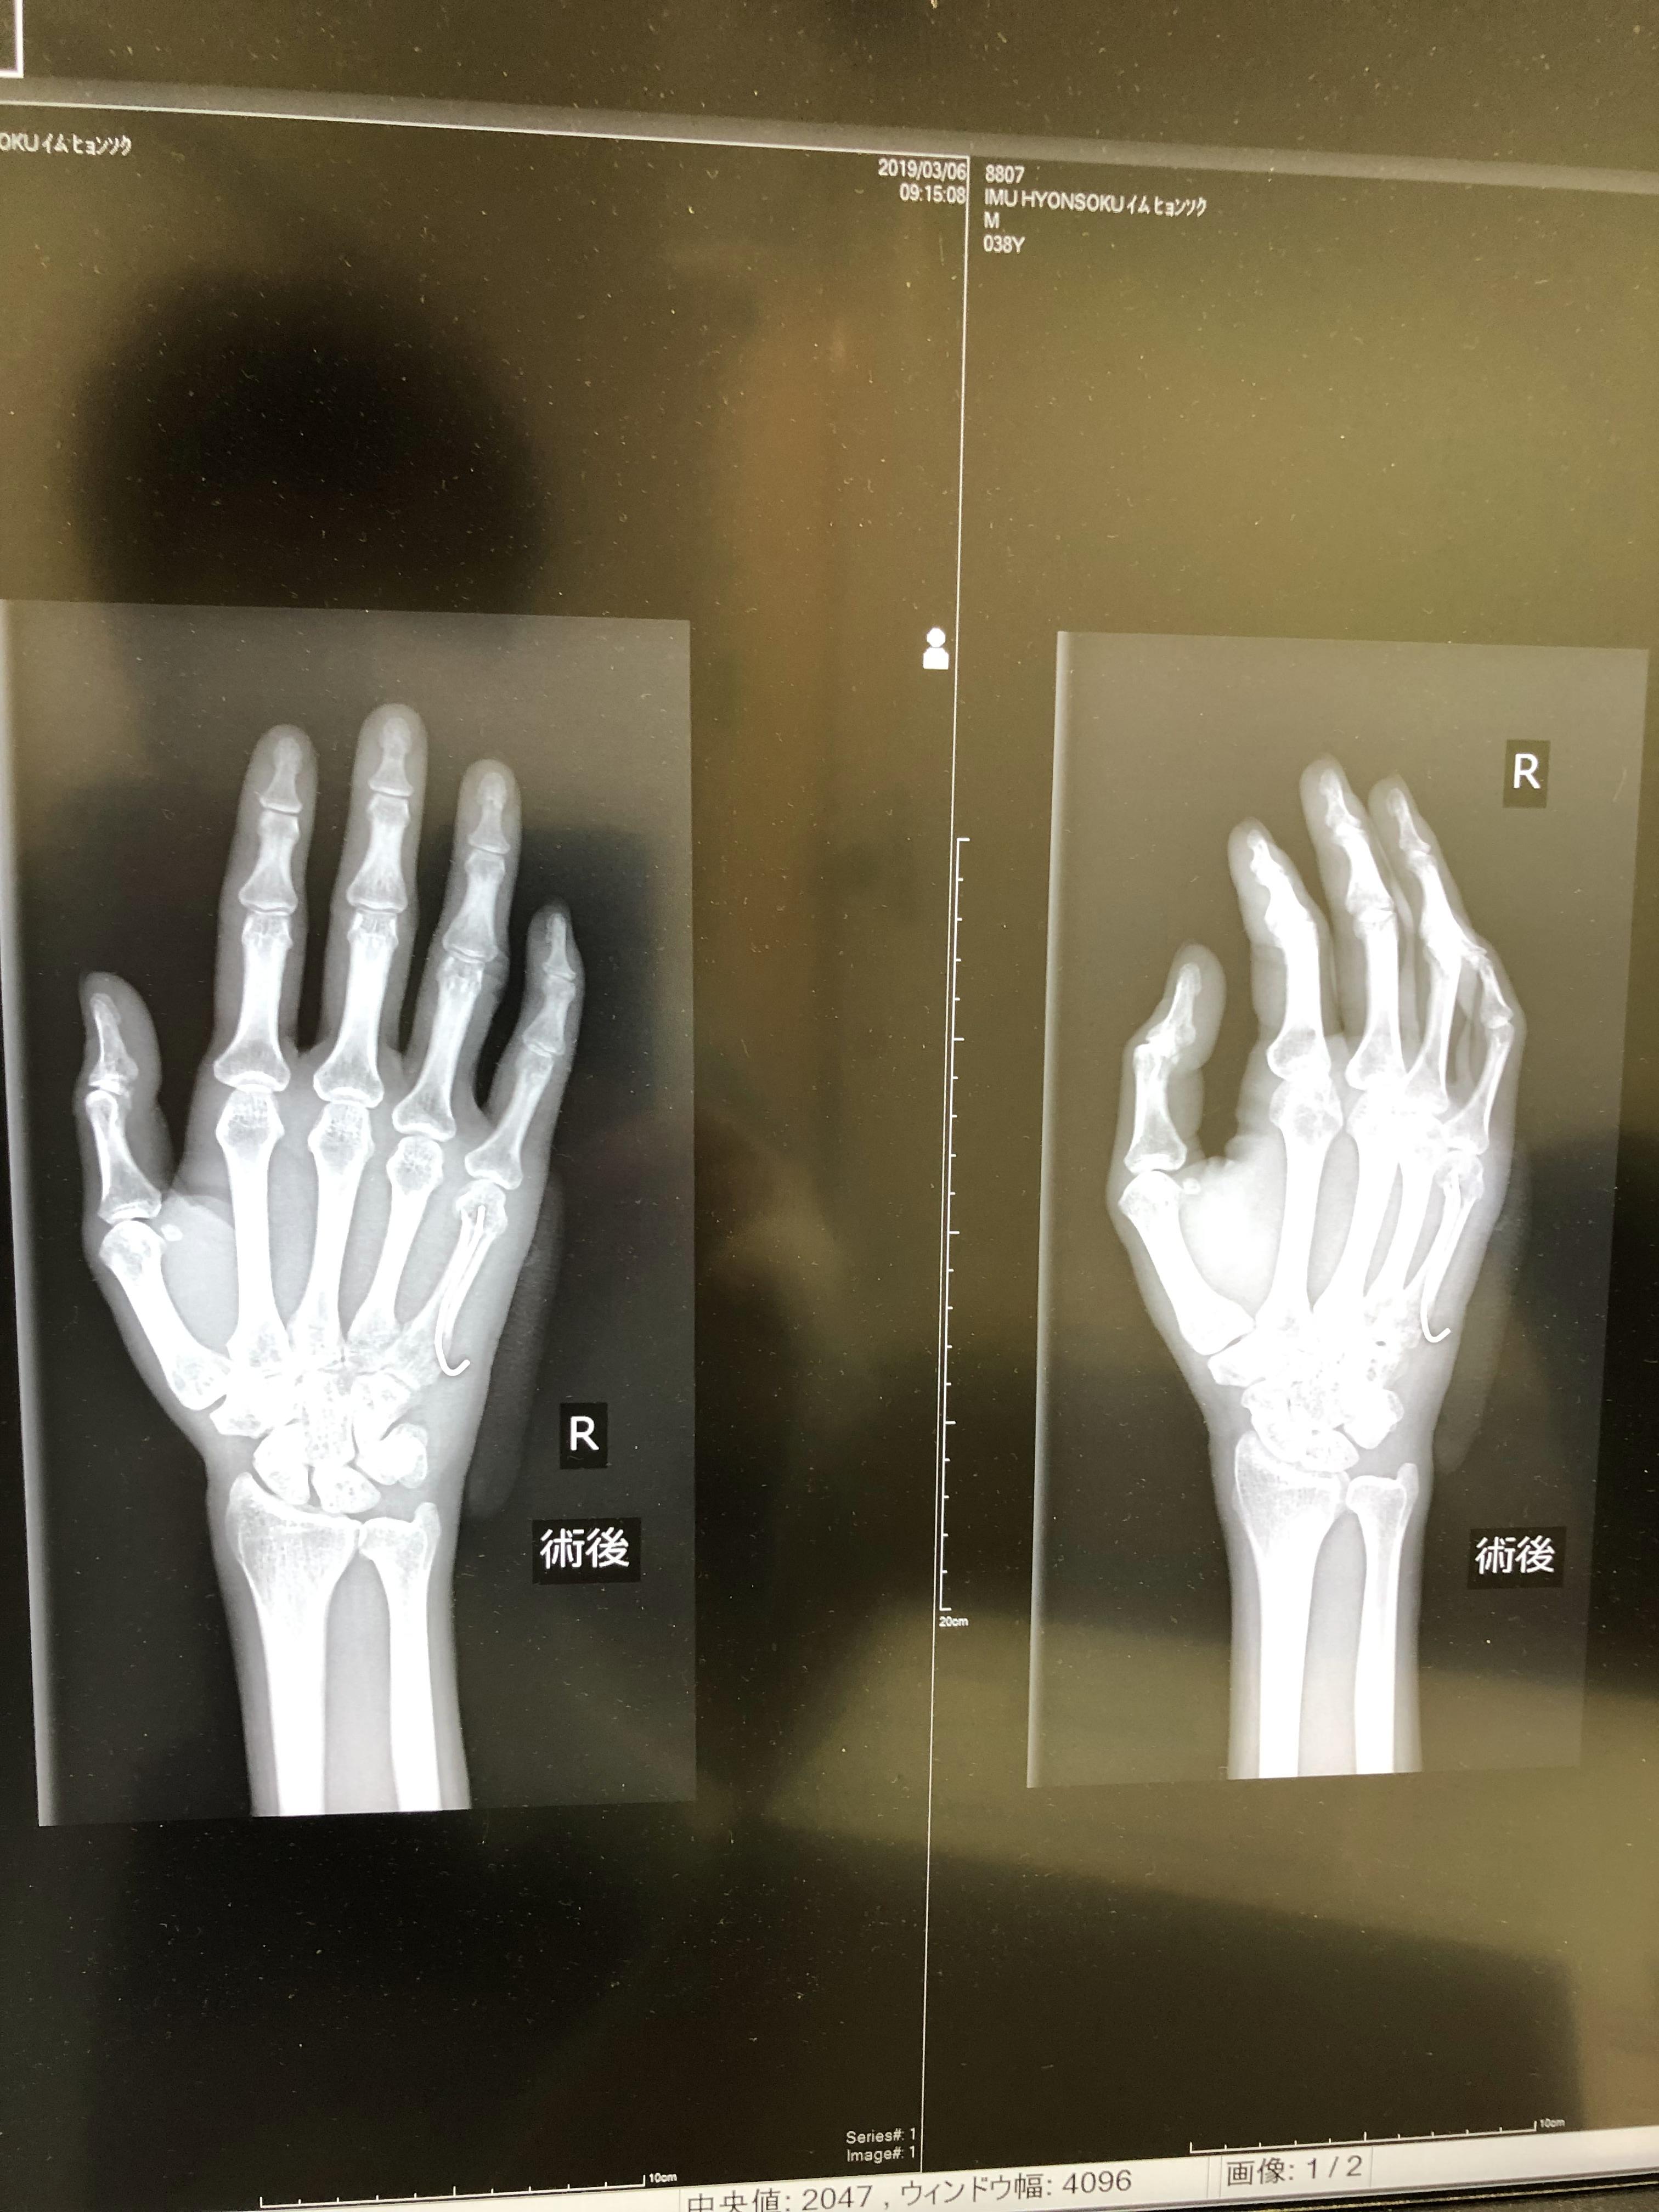

어찌저찌하다가 새끼손가락 뼈가 휘여서 철심을 박았습니다. ㅠ.ㅠ

보이시나요? 새끼손가락 안에 들어간 저 철심 ㅠ.ㅠ

하..... 어쩌다가 이리 됐는지....